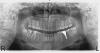

Алексей, спасибо за ответ. Исходная ситуация в прикрепленных фото.

Если причина нынешнего рецидива в том, что из-за удаления 4-к верхняя зубная дуга стала короче нижней, то как теперь это можно исправить?

Кстати, в 2010 году, перед началом лечения, я задала вопрос об удалении здесь на этом форуме, и мне ответили, что удаление премоляров на ВЧ - это стандартный, общепринятый и, в моем случае, правильный план.